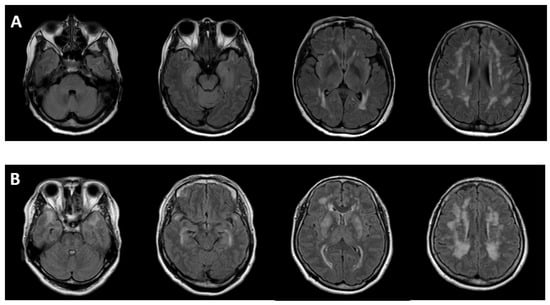

2.5. Imaging Differences